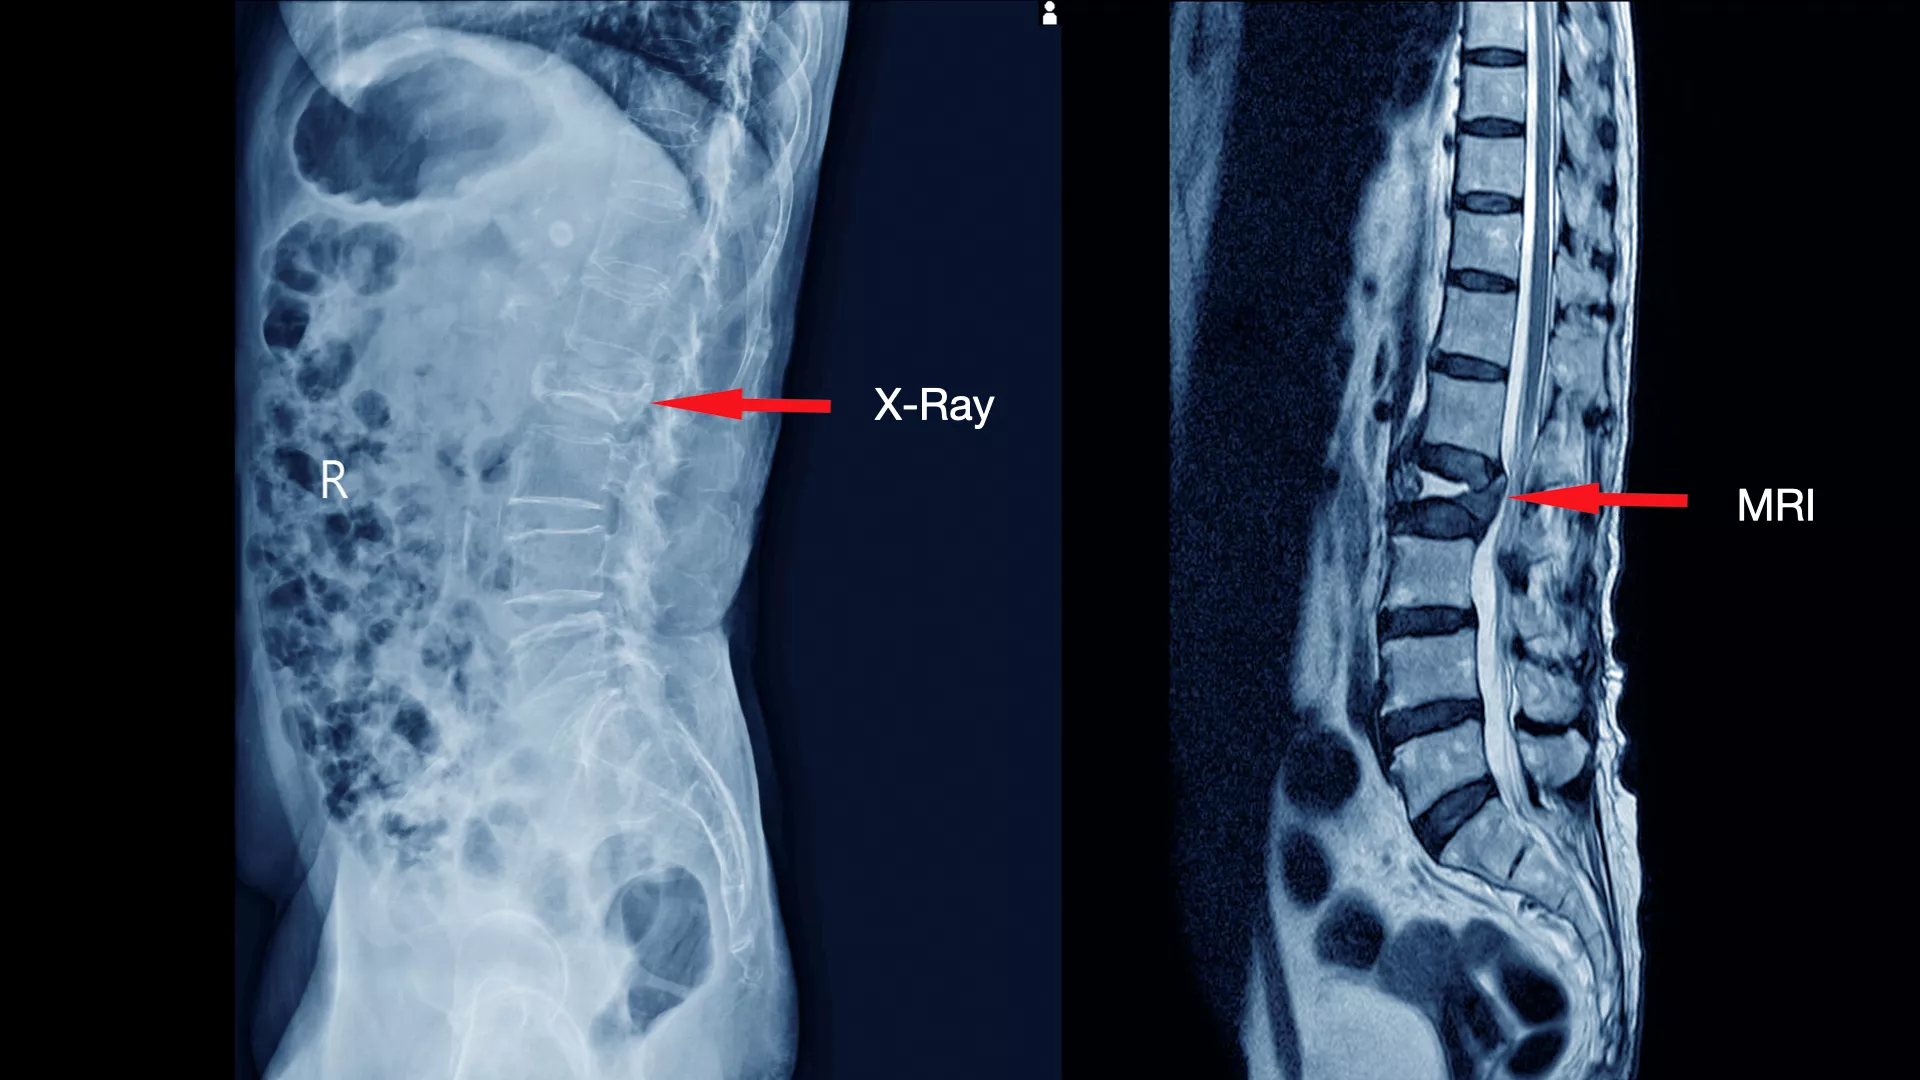

การตรวจด้วย X-ray ทั้ง 4 ท่าจะช่วยให้แพทย์ประเมินภาพรวมของโครงสร้างกระดูกได้อย่างละเอียด แต่ X-ray ไม่สามารถแสดงภาพของเนื้อเยื่ออ่อน (Soft Tissue) เช่น หมอนรองกระดูก เส้นประสาท และไขสันหลัง ได้อย่างชัดเจน

ดังนั้น การตรวจด้วย MRI จึงเข้ามาเติมเต็มในจุดนี้ โดยจะะให้ภาพที่มีความละเอียดสูงและสามารถเห็นรายละเอียดของเนื้อเยื่ออ่อนและลักษณะของรอยโรคได้อย่างชัดเจน ทำให้แพทย์สามารถ

- ระบุตำแหน่งและขนาดของรอยโรคได้อย่างแม่นยำ เช่น หมอนรองกระดูกปลิ้น หรือ หมอนรองกระดูกทับเส้นประสาท

- ประเมินความเสียหายของเส้นประสาท เห็นถึงระดับการกดทับของเส้นประสาทและไขสันหลัง

- วางแผนการรักษาได้อย่างถูกต้อง ช่วยให้แพทย์ตัดสินใจได้ว่าควรใช้วิธีการรักษาแบบไม่ผ่าตัด เช่น กายภาพบำบัด ทานยา หรือจำเป็นต้องผ่าตัด

การตรวจทั้ง X-ray และ MRI ร่วมกันจึงเป็นการผสมผสานที่สมบูรณ์แบบ เพื่อให้แพทย์ได้ข้อมูลที่ครอบคลุม ครบถ้วนและแม่นยำที่สุด สำหรับการวินิจฉัยและวางแผนการรักษาที่เหมาะสมสำหรับผู้ป่วยแต่ละราย